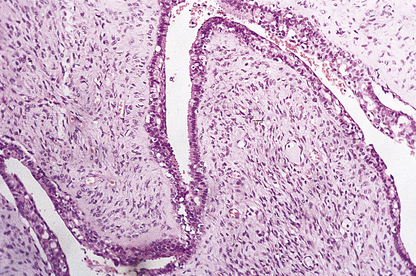

Gynaecomastia is benign enlargement of the male breast tissue. The breast may resemble that of a young adolescent female in appearance and consistency, or there may be a firm, mobile disc beneath the nipple. The condition is unilateral in 75% of cases. The ducts are dilated and there is a variable degree of epithelial proliferation. The stroma around the ducts is often oedematous and myxoid, but in longstanding cases the stroma becomes dense and hyalinised (Fig. 18.11).

image

Fig. 18.11 Gynaecomastia. Male breast in which the ducts are lined by an increased number of cells, and are surrounded by loose connective tissue.